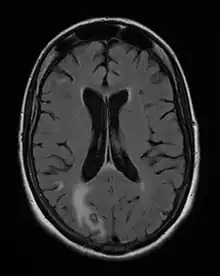

La toxoplasmose cérébrale est une maladie opportuniste dont la survenue chez les personnes séropositives marque l'évolution de l'infection par le VIH au stade de sida. Elle survient en règle générale chez des sujets séropositifs au VIH, ayant moins de 200 lymphocytes T CD4+, avec une sérologie toxoplasmique positive et ne recevant pas de prophylaxie spécifique. C'est alors que les bradyzoïtes libèrent les tachyzoïtes qui essaiment dans tout le corps via le système sanguin[37]. En 2008 en France, la toxoplasmose cérébrale représentait 12 % des personnes qui découvraient leur séropositivité au VIH après le déclenchement d'une affection opportuniste[38].

Les symptômes de début peuvent être insidieux, céphalées d'installation récente ou réactivation de céphalées anciennes, avec ou sans fièvre. Trois situations sont possibles :

- il s'agit d'un (ou de plusieurs) abcès cérébral (cas le plus fréquent) donnant un tableau neurologique rapidement progressif. Les signes cliniques dépendent de la localisation de(s) l'abcès : hémiplégie ou hémiparésie, syndrome cérebelleux, aphasie, amputation du champ visuel, ou signes plus diffus à type de somnolence, désorientation, crises comitiales ;